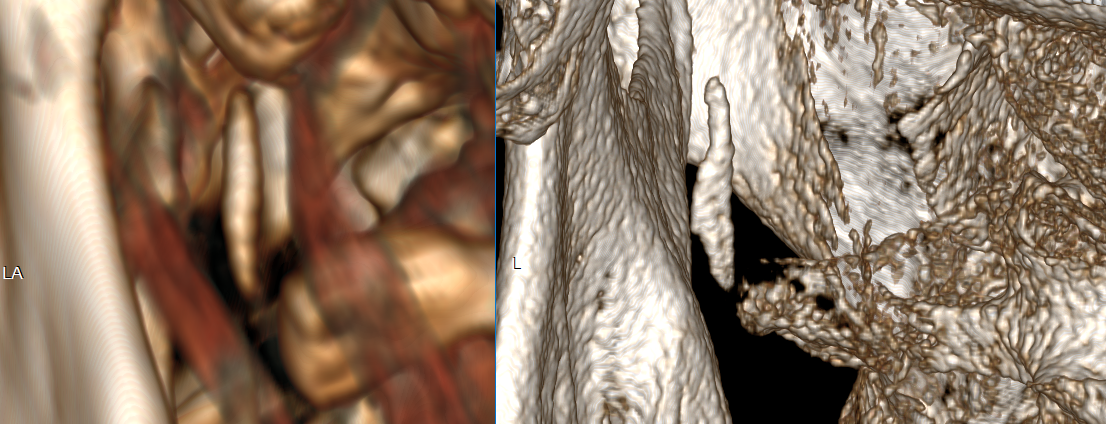

3D views – one is low-res from above CT, and another is high-res from a CT with 0.2mm slices (most detailed CT I’ve ever seen). Distance from C1 is measured at about 1.5mm, length of calcified portion is ~15mm and it is flatter on one side in the lower section, with a “bit” sticking out slightly.